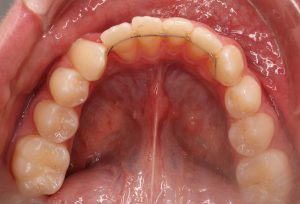

* 2 zgornja in spodnja retencijska žička

*2.Retencijske žičke so v uporabi od leta 1970. Fiksacija zob z retencijsko žičko, ki je nalepljena na notranji strani zob, se je izkazala za zelo priljubljeno, saj prepečeuje premike zob, kjer je recidiv zelo verjeten in snemni retencijski aparati niso zanesljivi, prav tako ni potrebno pacientovo sodelovanje. Po množični in dolgotrajni uporabi pa se je izkazalo, da te žičke niso tako nedolžne in lahko pride do stranskih neželjenih učinkov.

Leta 2022 je bila narejena prva študija o stranskih učinkih retencijske žičke. V ortodonstkih krogih je pojav dobil ime WIRE-SINDROM. Nov pojem wire sindrom se nanaša na premike zob, ki jih je mogoče opredeliti kot nenormalne, nepričakovane, nepojasnjene ali prekomerne premike zob, ki jih še vedno drži nepoškodovana ortodontska retenerska žica brez odstopitve ali zloma, kar vodi do razvijajočih se estetskih in/ali funkcionalnih posledic, tako zobnih kot parodontalnih.

Primer iz naše ambulante

Wire sindroma je nov pojav in je zaskrbljujoč za ortodonte, splošne zobzdravnike in parodontologe predvsem pa za paciente. Pomembno je, da primere odkrijemo zgodaj in se takoj učinkovito preprečijo nadaljni neželeni premiki zob in z njimi povezane posledice za dento-parodontalno tkivo ter se odločimo za ustrezno terapijo. Sporočilo akademske stroke pa je, da so potrebne dodatne klinične študije za razjasnitev etiopatogenih mehanizmov žičnih sindromov in njihovih kliničnih vplivov, kar bo akademski stroki na koncu omogočilo, da kliničnim ortodontom predlagajo učinkovite preventivne ukrepe.